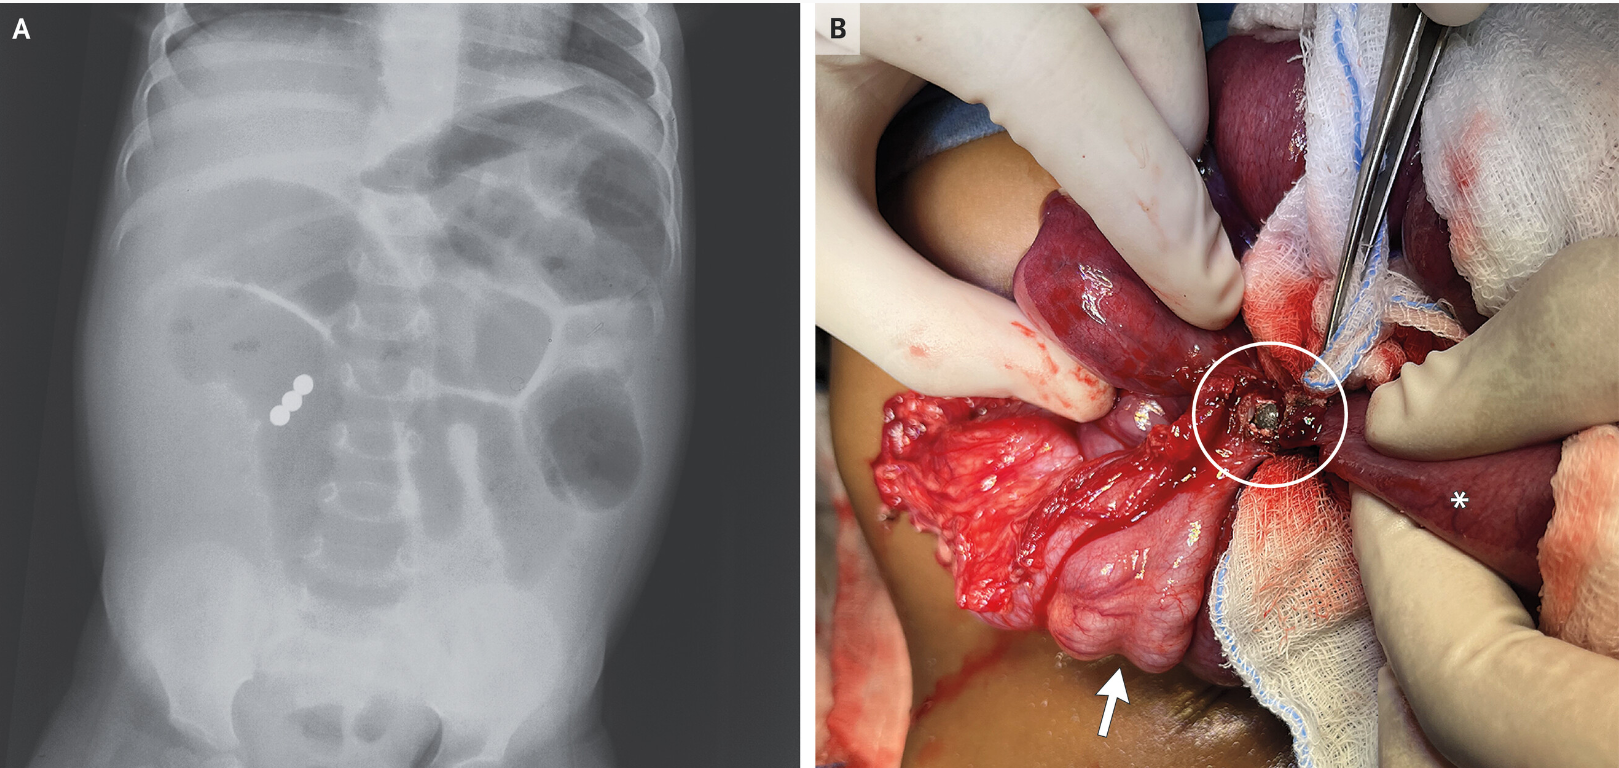

A previously healthy 18-month-old girl was brought to the emergency department with sudden-onset abdominal distention that had been preceded by 3 days of diarrhea and 1 day of vomiting…an emergency exploratory laparotomy was performed. An ileocecal fistula (Panel B, circle) created by the union of three magnetic beads was identified (arrow, cecum; asterisk, ileum), and dilated loops of bowel were noted. The bowel was repaired. The patient was discharged after five days.